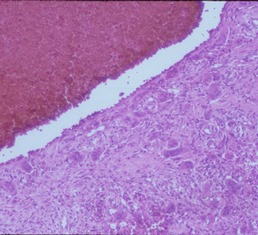

Microscopic Pathology

- Hemorrhagic tissue with large cavitary spaces divided by septum of spindle fibroblastic cells, inflammatory cells and few giant cells.

- Osteoid formation could be noted (reactive and benign in nature)

Fig 3 a,b,c. Microscopic pathology of an Aneurysmal Bone Cyst (ABC):

Figure 3a: There is a large blood filled cystic cavity surrounded by a fibrous septae that includes benign appearing spindle cells, fibrous extracellular matrix and scattered giant cells. There are areas of reactive bone formation. The fibroblastic cells are bland appearing. There are no abnormal mitotic figures.

Fig 3b: Intermediate power of a septum of an ABC: There is no epithelial lining around the wall of the cavity filled with blood. There are spindle cells and scattered giant cells.

Fig 3c: High power view of an ABC: Demonstrates reactive bone formation within the wall of the cystic cavities. This is reactive bone and different from the lace like immature bone layed down by an osteosarcoma